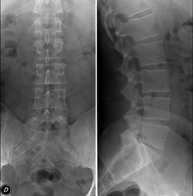

- RX Columna lumbar

Técnica mediante la cual, utilizando rayos X, se obtienen imágenes de la columna lumbar para su estudio.

Técnica mediante la cual, utilizando rayos X, se obtienen imágenes de la columna lumbar para su estudio. Indicaciones: ciática, traumatismo, dolor lumbar.